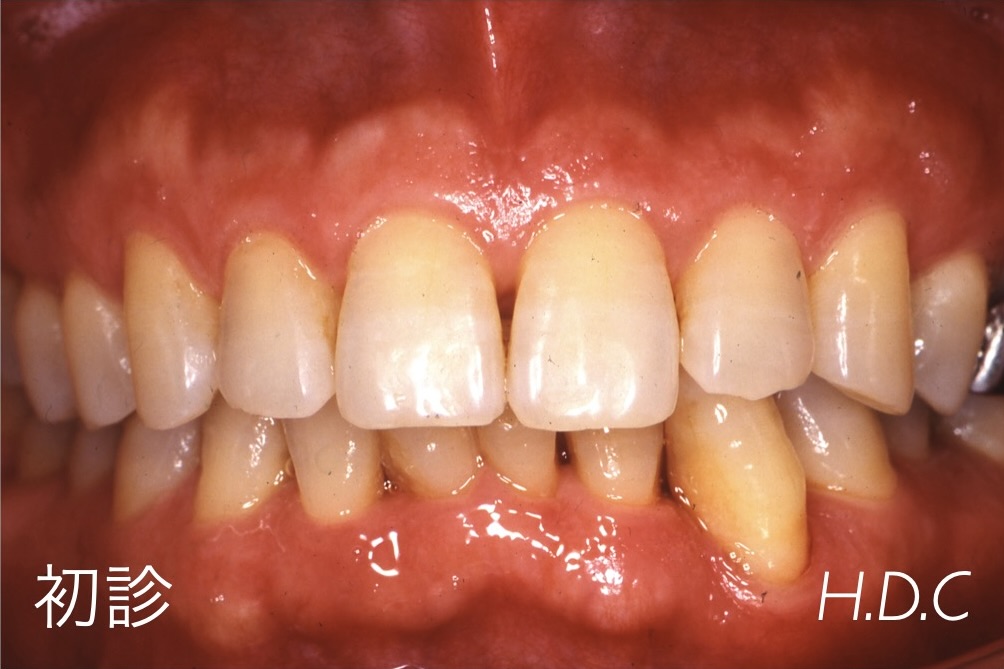

歯周病治療例③

(GTR法による再生治療症例)

- 年齢・性別

- 30代 女性

- 主訴

- 上の前歯がグラグラする。

- 診断名

- 重度歯周病(広汎型慢性歯周炎 Stage Ⅲ Grade B)

- 治療内容

- 他院で抜歯と診断された重度歯周病の上顎前歯に、歯周組織再生治療(GTR法)後、セラミック冠による補綴治療を行いました。

- 治療期間

- 約2年

- 治療費用

- 歯周外科治療(GTR法)保険診療(現在、当院ではGTR法は保険診療では行なっていません)補綴治療 ¥504,000 セラミック冠・ファイバーコア4本(2007年診療時)

- リスク

- 歯周組織再生療法時の出血・腫脹・青痣、歯肉退縮、セラミック冠の破折、脱離など